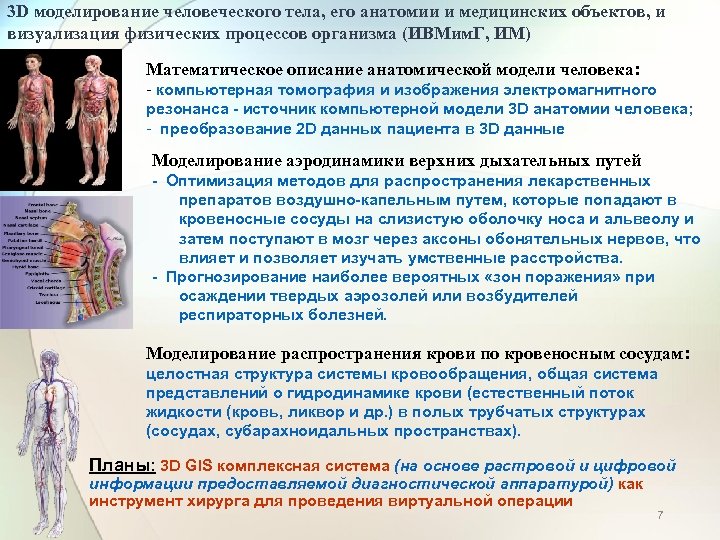

Моделирование физических процессов: примеры и схемы